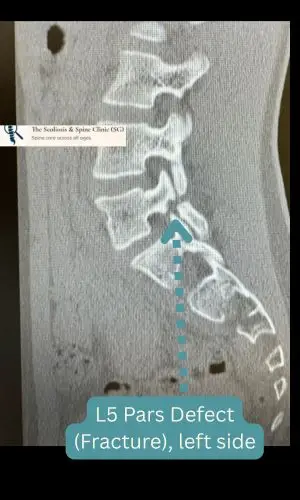

Diagnostic Imaging

Axial CT scan revealing bilateral pars defects at L5 in a 14-year-old ballet dancer.

Advanced imaging confirmed bilateral L5 spondylolysis.

This wasn’t a fresh injury. All signs pointed to a fracture that had been present for some time, likely sustained through repetitive stress and extension during ballet training. There were no dramatic falls. No single moment of trauma. Just the cumulative toll of movement – the precision, and discipline— etched into the architecture of her spine and chipping away the bones at its weakest link – at the bony bridge that spans across the upper and lower joints.